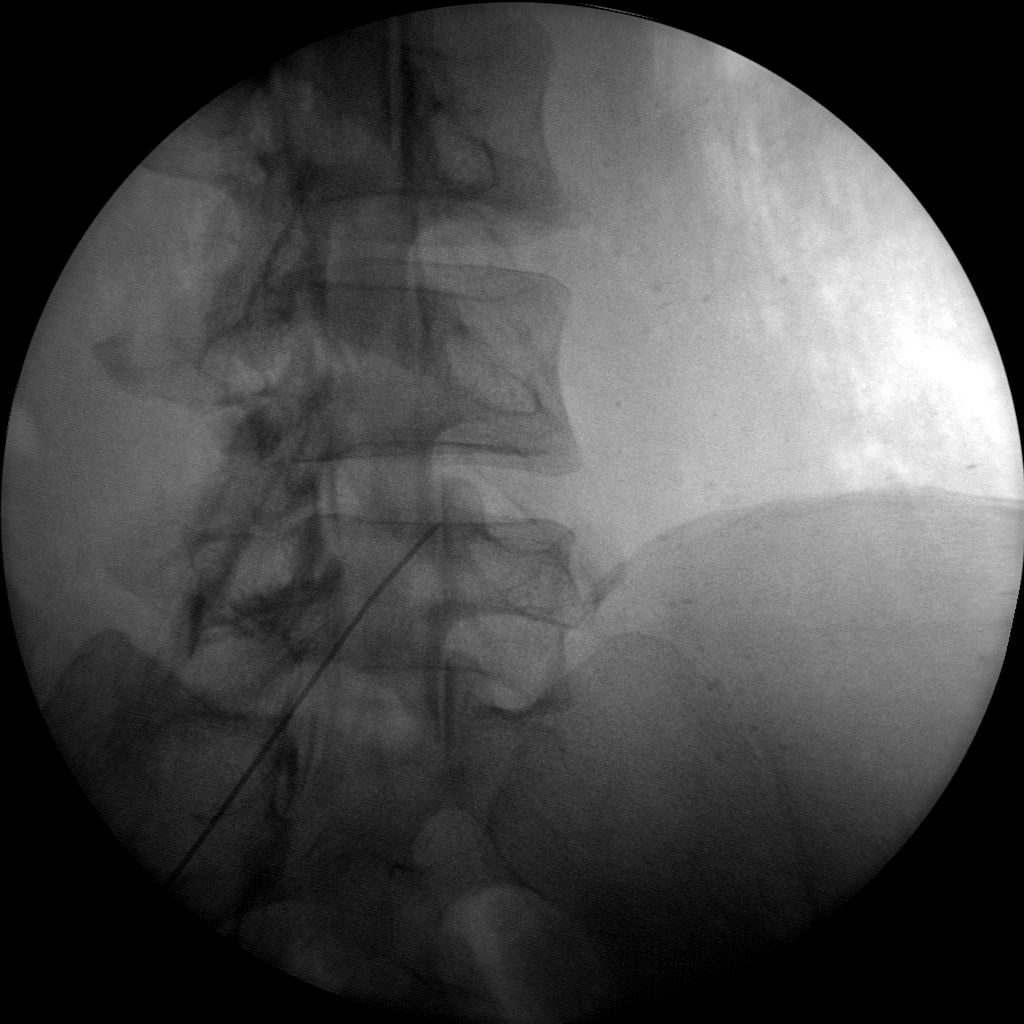

Radio frequency Ablation (RFA)

Skan-C is an invaluable tool for performing Radiofrequency Ablation (RFA), a procedure that uses heat to disable nerves responsible for transmitting pain signals. Skan-C's advanced imaging capabilities facilitate precise localization of the target nerves, guiding the placement of the RFA needle electrode accurately.